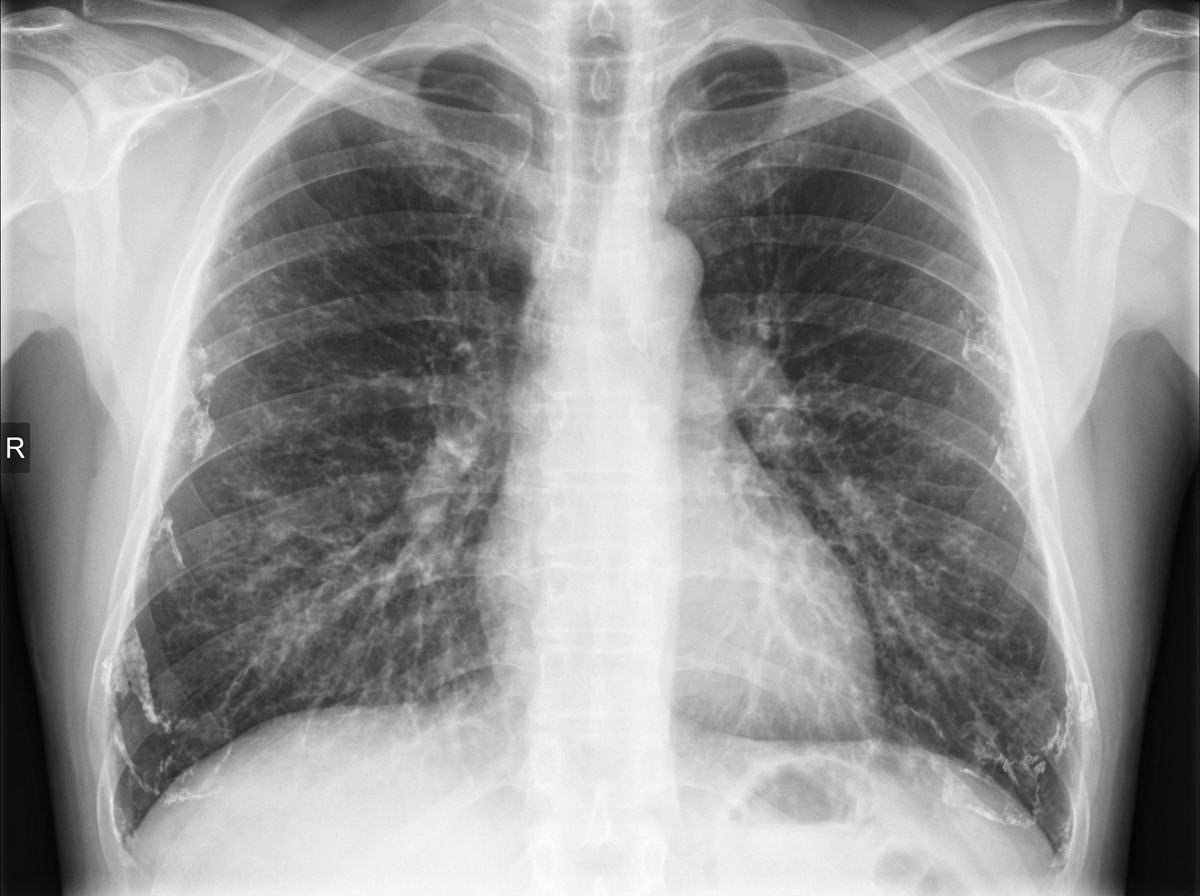

A 45-year-old man with a 15-year history of working in a construction factory presents with a 6-month history of cough. What is the probable diagnosis based on his chest X-ray findings and occupational history?

Explanation: ***Asbestosis*** - **Construction factory** work for 15 years provides significant **asbestos exposure** risk, as asbestos was commonly used in building materials until the 1980s. - Chronic cough developing after prolonged exposure is consistent with **asbestos-induced pulmonary fibrosis**, typically showing **bilateral lower lobe reticular opacities** and **pleural plaques** on chest X-ray. *Silicosis* - Associated with **silica dust exposure** from occupations like **mining**, **sandblasting**, or **quarrying**, not typical construction work. - Chest X-ray characteristically shows **upper lobe nodular opacities** and **progressive massive fibrosis**, contrasting with lower lobe involvement in asbestosis. *Anthracosis* - Results from **coal dust exposure** in **coal miners** or workers in coal-processing industries, not construction factories. - Presents with **black lung** appearance on imaging with **coal macules** and **progressive massive fibrosis**, typically in upper zones. *Mesothelioma* - While associated with **asbestos exposure**, it is a **pleural malignancy** that typically presents with **chest pain** and **dyspnea** rather than just cough. - Chest imaging shows **pleural thickening** and **pleural effusion** rather than the **pulmonary fibrosis** pattern seen in pneumoconioses.